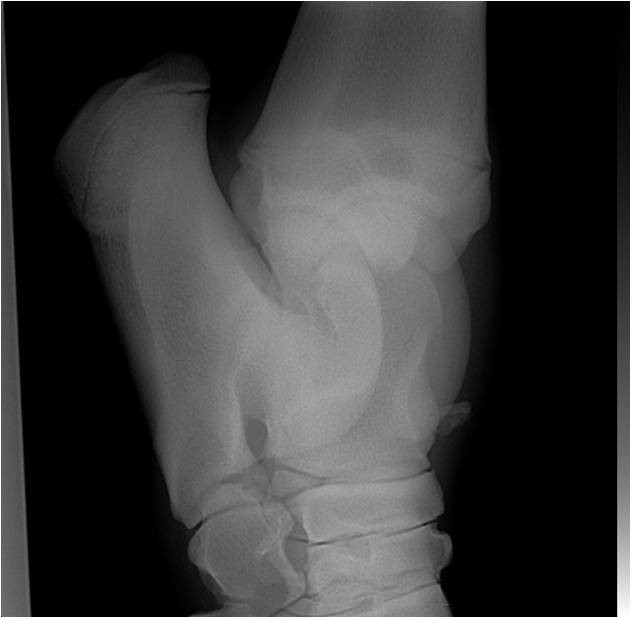

OCDTarsus